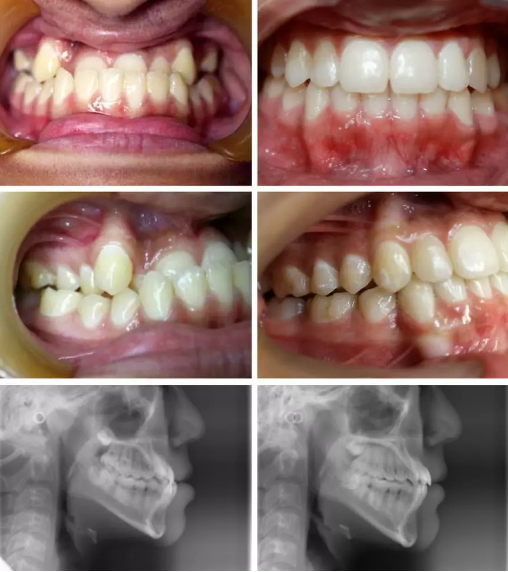

侧面(阴影是整之前,白色是整之后)

正脸

张嘴笑

细心的观众们看出来我的变化了吗???

有点的时候还有人问我,这条朋友圈的重点在哪里?是说瘦了吗?哇大哥,真的是没有下巴短嘴凸的痛处的人是体会不到这个巨变的!

当然大部分的人都是说,整牙真的能这样?黄医生真的是我的再生父母啊!让我举一杆大旗子感谢他的再造之恩~